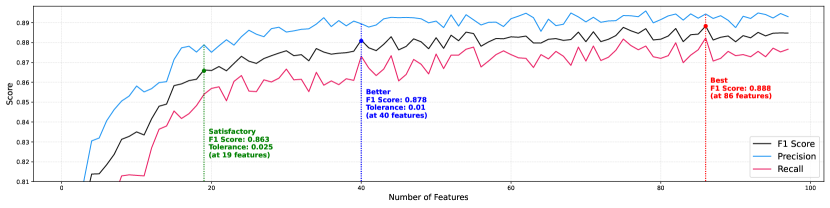

Due to the potential for performance degradation in ML training caused by a high number of features, which could also result in generating insignificant scenarios during counterfactual generation, we aimed to minimize the number of features. To achieve this, we initially employed the recursive feature elimination (RFE) method with the default XGBoost (XGB) algorithm, using the objective parameter ‘binary:logistic’ and the booster parameter ‘gbtree’ with default tree parameters. This process identified 97 features as rank 1. We opted not to perform hyperparameter optimization for the XGB model due to computational constraints, preliminary results indicating that default parameters were sufficient, and our focus on feature engineering instead of model tuning. We believe that this decision was appropriate given the specific context and goals of our research. Following the feature selection, the chosen 97 features underwent further assessment, and their ranking was adjusted based on their importance within the XGB framework (Appendix Figure C.5). We then took a systematic approach to training the model, starting with just 1 feature and gradually adding more, up to the full set of 97 features, documenting the outcomes at each step (Figure 3).

5.1 Feature Elimination and XGBoost Classification

For the training of the ML model, our initial step involved employing RFE on XGB to reduce the number of features. This process assigned a rank of 1 to 97 features, and we proceeded with our analysis using this subset of selected features. In subsequent stages of our analysis, we computed the importances of these chosen features within the XGB, as depicted in Appendix Figure C.5.

Following an in-depth examination of the selected features, we organized them based on their respective importance scores. Then, we conducted further training on XGB, progressively augmenting the number of features employed in the model (Figure 3). As depicted in Figure 3, we can observe that having a mere 2% score tolerance enables us to reduce the feature count from 86 to 19. This reduction brings benefits when working with counterfactuals.

Through our experimental investigations, we discovered that utilizing 19 features is sufficient for extracting counterfactual instances. A lesser number of features is preferable for counterfactuals as it yields better and more reasonable explanations. To conduct a comprehensive assessment of counterfactuals, we generated distinct scenarios involving sets of 5, 10, 15, and 20 features. This evaluation encompassed considerations such as the time taken for generation (refer to Appendix Figure C.6 and C.7) and a comparative analysis of the most influential features affecting the outcomes. The F1 scores for each feature set are as follows: 81.40% for 5 features, 83.50% for 10 features, 85.83% for 15 features, 86.59% for 20 features, and 88.47% for 97 features.

Upon closer examination of the selected features, we observed that the II_R feature could independently distinguish numerous cases with an accuracy of 76.16%. Furthermore, it is evident that features like aVF_R, V3_R, V4_R, V1_S, II_T, aVR_T, V3_ST, and aVF_ST_mean exhibit a notably higher level of effectiveness, even visually, compared to the remaining features (see Appendix Figure C.5).

In the initial set of five features, we identified II_R, II_T, V4_R, V3_R, and aVF_R features, which collectively contributed to an 81.40% accuracy in distinguishing between MI and NORM cases. Extending the feature count to 10, we additionally recognized V1_S, aVR_T, V3_ST, aVF_ST_mean, and V1_RS features, collectively contributing to a score of 2.1%. With the inclusion of 15 features, the score exhibited a further increase (2.33%). Notably, within this set, the model selected features such as V1_PS, aVF_QS, V1_QS, V1_ST, and RR_Next, indicating their significant contributions. Lastly, in the 20-feature set, we observed the presence of features like V4_PT, V2_Q, V1_T, V5_T, and aVL_RS.

R-wave amplitude stands out as a prominent feature in the initial set of features (4 out of 5). We also observe the importance of T-wave amplitude in lead II and aVR, as well as S-wave amplitude in lead V1. Additionally, we notice T-waves with a lesser impact in V1 and V5 leads. In the case of V3 and V1, we observe various peak relationships, specifically the differences between S-amplitude and T-amplitude at V3, R-amplitude and S-amplitude, P-amplitude and S-amplitude, Q-amplitude and S-amplitude, as well as S-amplitude and T-amplitude at V1.